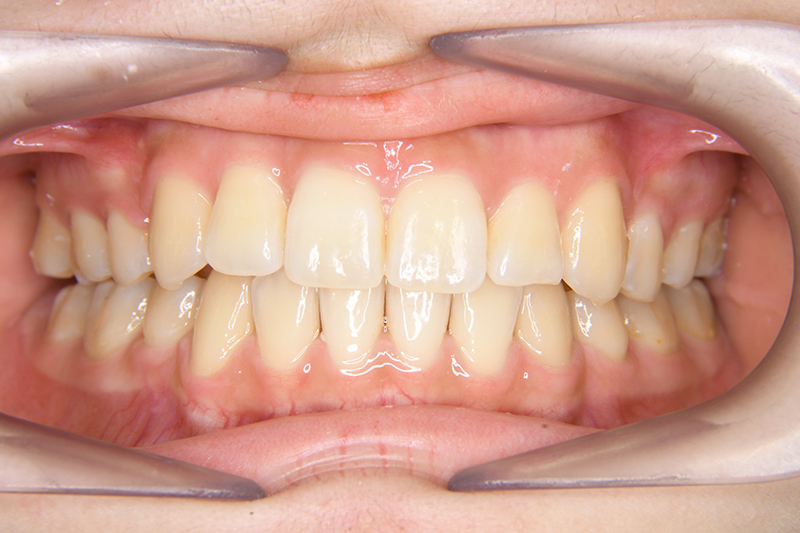

| 口腔内所見 | over jet 3.8mm、over bite 30mm、臼歯関係I級、上下顎前歯部に叢生が認められ、下顎正中は右側へ4.5mm偏位していた。左上5はCRの治療痕が認められた。 |

| 批評・予后 | 治療後において閉唇時の頤筋の過緊張の改善及び咬合の緊密化と歯根のパラレリングが認められ、良好な咬合が確立できたと思う。 現在は保定をしつつ下顎両側第三大臼歯抜歯の抜歯を検討している。 |